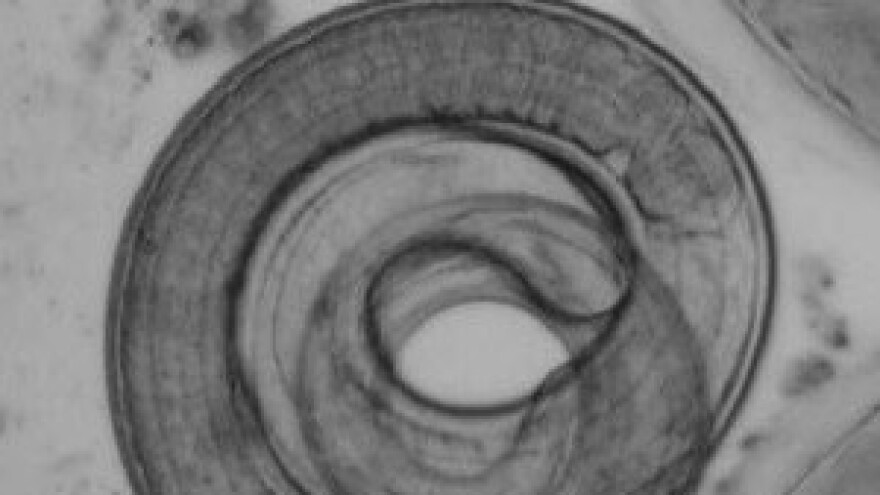

Trihineloza je parazitarna bolest ljudi i životinja (zoonoza), koju uzrokuju obli paraziti iz roda Trichinella, najčešće vrste Trichinella spiralis, koja u zaraženih svinja, za razliku od čovjeka, najčešće prolazi bez simptoma.

Iako se trihinela može pronaći u mesojedima i svejedima, za čovjeka je najvažnija karika u prijenosu bolesti upravo svinja. Svinja se najčešće zarazi jedući različite vrste glodavaca (te ostatke zaraženog svinjskog mesa sa klaonica, što je sve češći put prijenosa), a čovjek jedući nedovoljno termički obrađeno svinjsko meso (prvenstveno kobasicu, kulen i šunku). Nakon unosa zaraženog mesa u probavni sustav čovjeka, iz čahura (ciste) se oslobađaju ličinke koje u prednjem dijelu probavnog sustava sazrijevaju, te prelaze razvojne faze do nastanka novih ličinki koje probijaju stjenku crijeva, ulaze u krv i limfu te se rasprostranjuju po tijelu čovjeka gdje stvarju čahure.